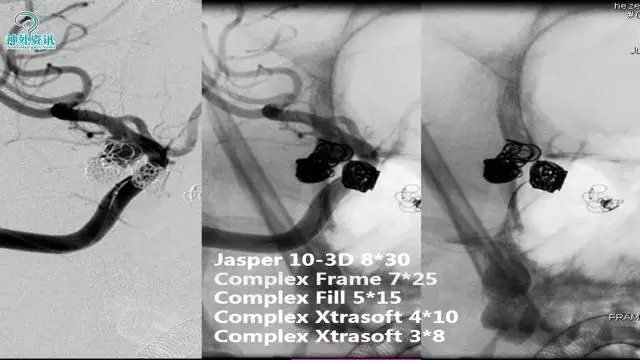

今天为大家分享的是“强生医疗CNV-神经介入专栏”第三十六期,由重庆第三军医大学附属新桥医院神经外科刘俊带来的“Galaxy弹簧圈在不规则动脉瘤中的临床应用”精彩讲课视频及PPT,欢迎观看。文章仅代表作者个人观点,如有不同见解,欢迎同道斧正!